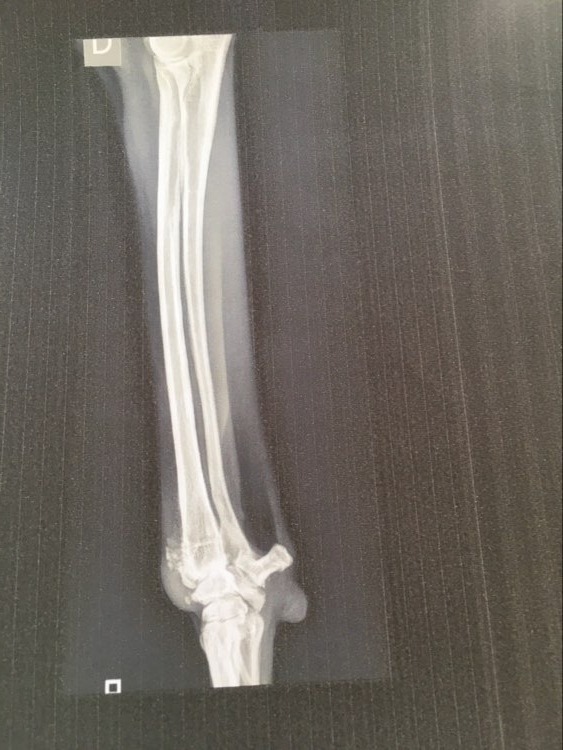

Les options thérapeutiques et la gestion conservatrice n'ayant pas données de bons résultats, il a été décidé le 30 Juin 2020 une prise en charge chirurgicale.

Une arthrodèse est donc programmée pour le Lundi 17 Août 2020.

Malgré une dernière tentative de traitement et la mise en place d'une orthèse pour soulager sa patte, Ana souffrait toujours et boitait de plus en plus.

Angelika et François, la famille d'accueil de Ana s'est vite aperçue qu'elle souffrait et une boiterie suite à la douleur s'est installée.

Nous avons essayé plusieurs traitements anti douleur mais aucun de ces traitements n'a apporté une amélioration satisfaisante.